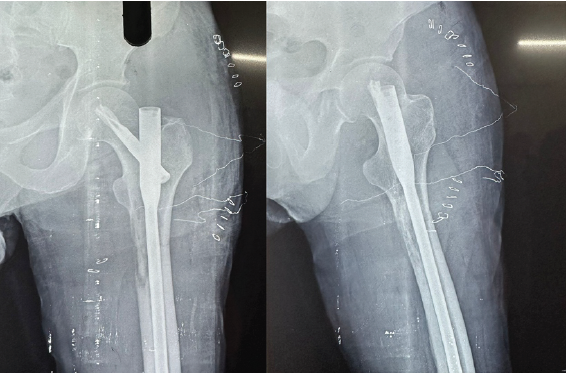

Plain radiograph of the left arm showed lytic lesion of the proximal shaft humerus (Fig. 5). Skeletal survey of the patient revealed multiple lytic lesions over the skull characteristic for multiple myeloma (MM). On further workup, Myeloma profile revealed a serum Calcium – of 7.7 mg/dL, serum beta-2 microglobulin – above 20,000 ng/mL, M band on serum protein electrophoresis.

Figure 5 : Plain radiograph of the left arm showing lytic lesion of the proximal shaft of humerus (89-year-old male with multiple myeloma). Skeletal survey revealed multiple lytic lesions over the skull characteristic of multiple myeloma involvement. The proximal humeral shaft location is the second most common site for long bone metastases and pathological fractures.

Intervention

Patient was managed with closed reduction and internal fixation using IM humerus nailing (Fig. 6) along with biopsy.

Figure 6 : Postoperative radiograph of the left humerus following closed reduction and internal fixation using intramedullary humerus nailing. The intramedullary nail provides stable fixation through the lytic lesion, allowing early mobilization and rehabilitation despite the patient’s advanced age (89 years) and systemic disease burden.

Radiograph of right arm shows pathological fracture of right shaft of humerus (Fig. 7).

Figure 7 : Plain radiograph of the right arm showing pathological fracture of the right shaft of humerus (55-year-old male with multiple myeloma for 3 years). The lytic lesion at the humeral shaft demonstrates tumor involvement characteristic of multiple myeloma-related pathological fracture.

Patient was managed with closed reduction and internal fixation using IM humerus nailing (Fig. 8) along with biopsy.

Figure 8 : Postoperative radiograph of the right humerus following closed reduction and internal fixation using intramedullary humerus nailing. The locked intramedullary nail secures the pathological fracture, enabling functional recovery and pain relief. The minimally invasive approach minimizes soft tissue trauma and operative morbidity.